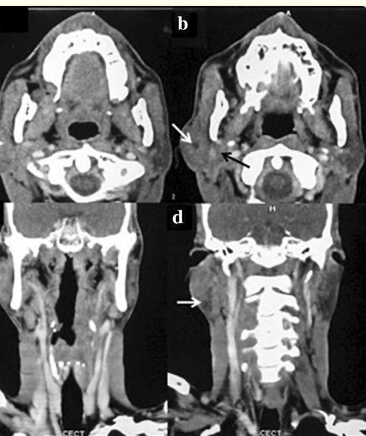

- The most common location is the parotid gland:

- Also the index case has parotid involvement:

- But it is also known to occur in submandibular gland and minor salivary glands of palate, base of tongue and rarely in breast, lung, kidney, uterus